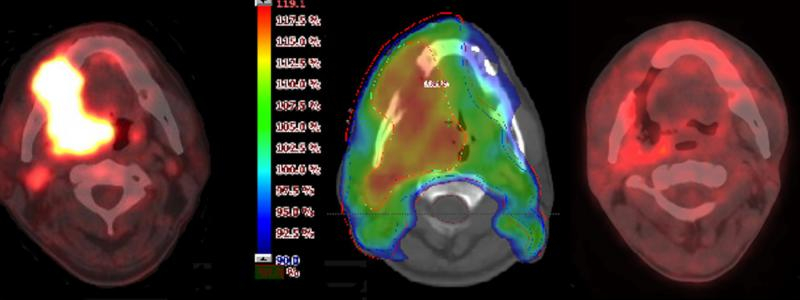

PET/CT je vyšetření, které spojuje dvě diagnostické metody - pozitronovou emisní tomografii (PET) a počítačovou tomografii (CT). Na přístroji jsou umístěny dva prstence těsně za sebou, jimiž pacient na lůžku projede. Zjištěné údaje lze pomocí počítače zkombinovat a výsledkem je obraz s velkou výpovědní hodnotou. „Toto vyšetření je jednou z nejpřesnějších diagnostických metod současné medicíny a může pomoci k důkladnější diagnostice onemocnění,“ uvedl Leoš Ungermann, primář radiodiagnostického oddělení Pardubické nemocnice.

Pozitronová emisní tomografie zobrazuje různé tkáně na základě jejich různé schopnosti akumulovat v sobě radioaktivní látku, která je nemocnému podána ve velmi malém množství a není tak pro něho nebezpečná. „Pacientovi je aplikována radioaktivní glukóza. Princip vyšetření spočívá v záchytu záření vysílaného z těla. V kombinaci s CT vyšetřením je pak možné přesně lokalizovat nádory,“ uvedl primář Ungermann a dodal: „PET/CT vyšetření je nejčastěji využívané v onkologii, kde slouží k vyhledání primárního nádoru a metastáz, ale i ke sledování efektu léčby. Využívá ho rovněž neurologie k lokalizaci ložiska v mozku zodpovědného za epilepsii či kardiologie. Dominantní je však onkologie.“